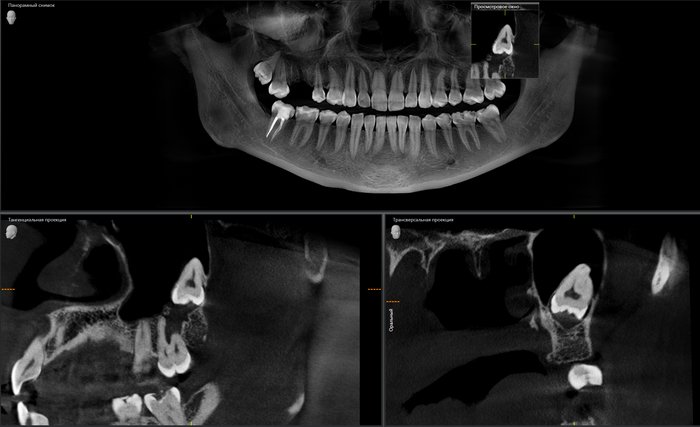

Когда же вы уже поймете, что для удаления подобных зубов:

требуется 20 минут, а никак не трехчасовой наркоз и трое суток в стационаре. (подобный случай я описывал подробнее в этой статье)

А для таких:

Чуть меньше часа (отдельно верх, отдельно низ):

В данном случае я очень долго и подробно рассказывал молодому человеку обо всех возможных осложнениях, особенностях восстановления и дальнейшем протезировании. Более того, я планирую написать полноценную статью по этому клиническому случаю, когда у пациента будут стоять имлантаты.